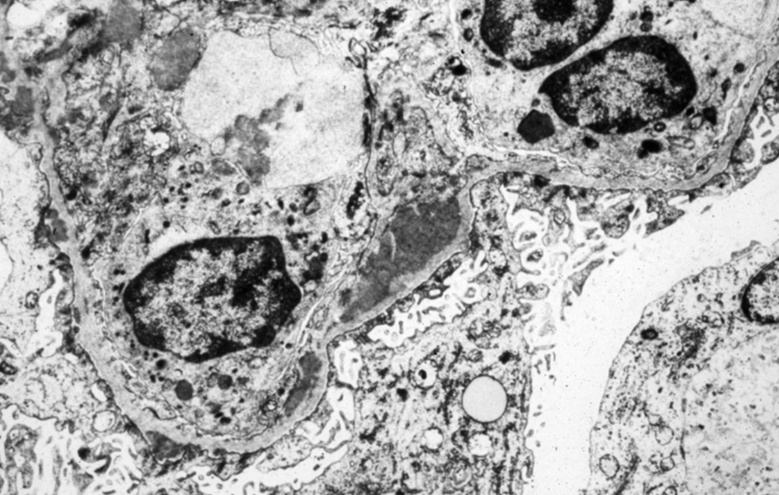

3 string: Associated with membranoproliferative glomerulonephritis. Tram track appearance

subendothelial deposits

electron dense deposits in basement membrane